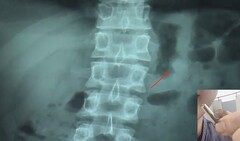

Медицинский персонал сделал рентгеновский снимок, на котором виден AirPod, уютно расположившийся в желудке незадачливого парня. Собственно, медицинская помощь г-ну Сюю заключалась в снабжении его слабительным, которое подействовало уже на железнодорожной станции, где владелец и воссоединился (или, наоборот, рассоединился?) со своим наушником. Следующая часть истории, скорее всего, понравится поклонникам Apple: после тщательной чистки и сушки AirPod, мужчина протестировал наушник на работоспособность, в результате чего выяснилось, что он не просто работает, а ещё и сохранил заряд на уровне 41%!